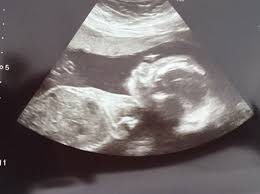

The median age at death is now the mid-50s compared. Down syndrome varies in severity among individuals causing lifelong intellectual disability and developmental delays. You may have an ultrasound between 18 to 20 weeks to evaluate dates a multiples pregnancy placenta location or complications.

The 20-Week Anatomy Scan May 2017.

Down syndrome is a genetic disorder caused when abnormal cell division results in an extra full or partial copy of chromosome 21. This test is done between 15 and 20 weeks of pregnancy. In 2011 a nicely done experiment by Marshall et al showed that regular hamstring stretching substantially increased range of motion in normal university kids95 Specifically after a 4-week stretching program consisting of 4 hamstring and hip stretches performed 5 times per week their range increased about 16 or 20. Down syndrome is a genetic disorder caused when abnormal cell division results in an extra full or partial copy of chromosome 21. In Down syndrome the nuchal translucency measurement is abnormally large as shown on the left in the ultrasound image of an 11-week fetus. How is a dating scan performed. The 20-Week Anatomy Scan May 2017.